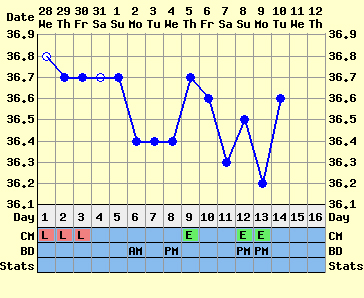

3 fázisúnak azt a görbét nevezik, amelyik úgy néz ki, mint a tied.

:D:D A ciklus első felében neked pl. 36,6 alatt van a hőd, pé. után felugrik 36,7-9, és aztán kezdődik egy újabb szakasz, amelyben még följebb áll be. Ezek igen gyakran babás görbék, mert a beágyazódás után észlelhető ez az újabb hőemelkedés.

De a görbéd így ránézésre is igen-igen biztató!!! Nagyon drukkolok!!!